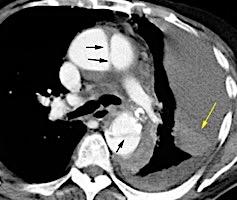

Signos radiológicos TC

Hallifax RJ et al. State-of-the-art: Radiological investigation of pleural disease Respiratory Medicine 2017

Nivel hidroaéreo o burbujas

Forma lenticular o elíptica Ángulos obtusos

> Grasa Extrapleural (60-80%)

Situación no gravitacional (no siempre)

Compresión de estructuras pulmonares

Límite muy bien definido Tabicación

Signo de la Pleura separada “Split pleural sign”

Capas pleurales de grosor uniforme realzadas por el contraste

No específico de empiema. Indica “exudado”. 68% de pacientes con empiema pleural.

Capas pleurales de grosor uniforme

Realce grasa extrapleural (30%)

> Grasa Extrapleural. (60-80%)

Kraus GJ. Split pleural sign. Radiology 2007